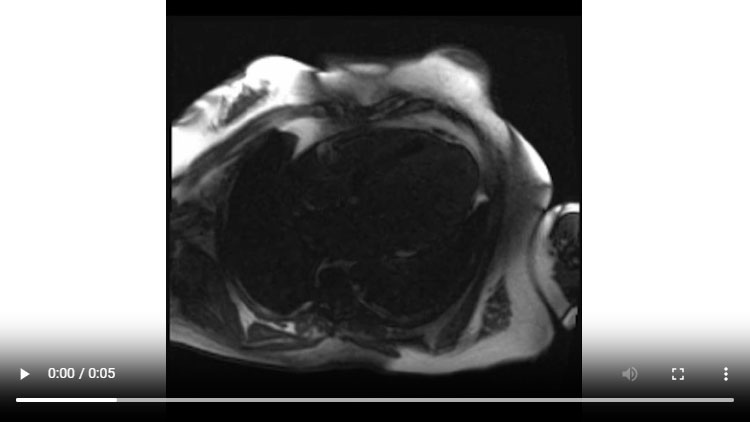

Figure 1D : Séquence Ciné-IRM - Coupes 2-cavités

- Présence d’une hypertrophie ventriculaire gauche (HVG) asymétrique à prédominance septale mesurée au maximum à 23 mm.

- Visualisation de la sonde de PM avec artéfacts métalliques modérés au niveau du ventricule droit (flèches roses).

- Présence d’un épanchement péricardique de moyenne abondance (flèches rouges).